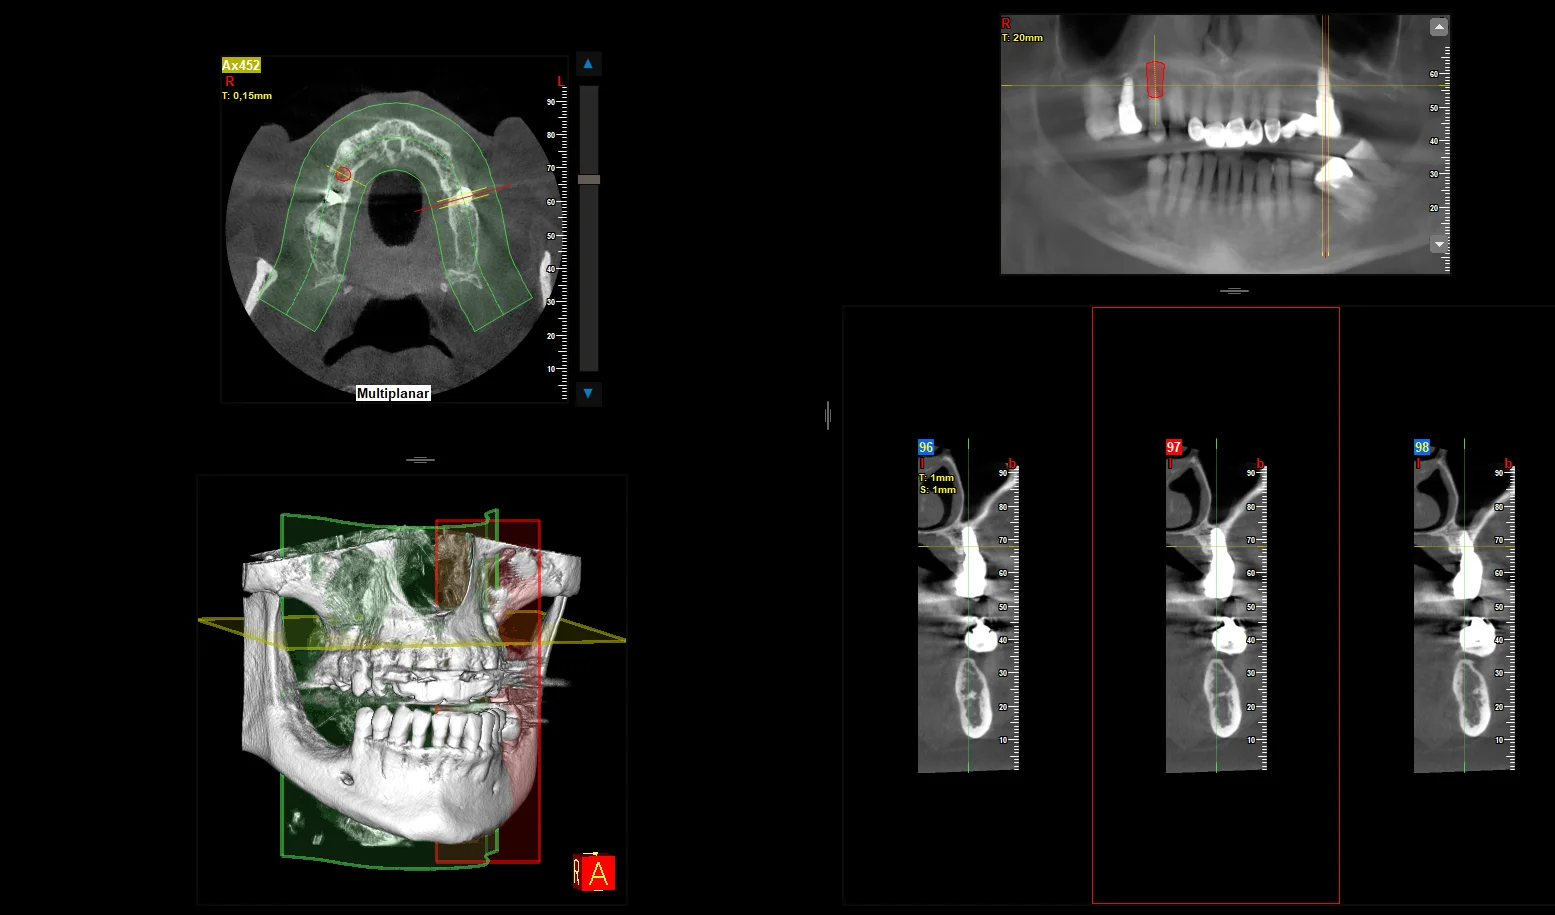

Każde leczenie implantologiczne poprzedzamy dokładną diagnostyką — analizą tomografii komputerowej CBCT 3D. Pozwala to precyzyjnie zaplanować zabieg, ocenić warunki kostne oraz dobrać odpowiedni typ implantu.